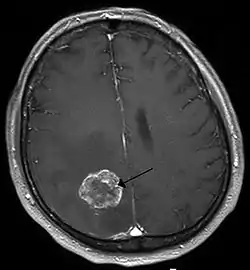

![]() انبثاث الورم الدماغي في نصف الكرة الدماغية الأيمن بسبب سرطان الرئة يظهر بالتصوير بالرنين المغناطيسي الموزون بT1 مع التباين داخل الوريد. انبثاث الورم الدماغي في نصف الكرة الدماغية الأيمن بسبب سرطان الرئة يظهر بالتصوير بالرنين المغناطيسي الموزون بT1 مع التباين داخل الوريد. | |

يتم فصل معظم خلايا الدماغ عن مجرى الدم عن طريق حاجز الدم في الدماغ (BBB)، الذي يمنع دخول جميع المركبات أو المواد في الدم إلى الدماغ. ولذلك يتم انتقال الورم إلى الدماغ فقط في حالة وجود خلل في حاجز الدم في الدماغ. والتي يمكن الكشف عنها بواسطة التصوير بالرنين المغناطيسي والتصوير المقطعي، ويعتبر المؤشر الرئيسي لتشخيص الاورام الدبقية الخبيثة، السحائية، والانعاثات الدماغية.[15]

التصوير

التصوير الطبي يلعب دورا محوريا في تشخيص أورام الدماغ. وقد تم التخلي عن الطرق القديمة الخطرة، مثل تصوير الدماغ المحقون بالغاز وتصوير الأوعية الدماغية واستبدلت بتقنيات عالية الدقة، والتصوير بالرنين المغناطيسي (تصوير بالرنين المغناطيسي) والتصوير المقطعي (تصوير مقطعي محوسب) بالاشعة. سوف تظهر الأورام غالبا للطبيب ملونة ومختلفة (كما يشار إلى العمليات) في نتائج CT أو MRI. • تظهر أورام الدماغ الحميدة غالبا على نحو أغمق من أنسجة الدماغ الطبيعية على الأشعة المقطعية(CT) . اما على MRI فإنها تظهر إما غامقة أو بنفس الشدة كما في أنسجة المخ على T1-weighted scans ، أو (أكثر إشراقا من أنسجة المخ) T2-weighted scans ، على الرغم من أن مظهرها متغير. • عند امتصاص الدماغ لكيماويات تسمى (عوامل التباين)، يمكن الكشف عن معظم أورام الدماغ الأولية والاورام الثانوية (النقيلية الخبيثة) في أي من الأشعة المقطعية أو الرنين المغناطيسي. • مناطق الضغط التي تم فيها الضغط على أنسجة الدماغ من الورم تظهر بشكل مشرق على T2-weighted scans، وربما تدل على وجود ورم منتشر بسبب الحدود الغير واضحة المحيطة بالورم. يمكن وجود انتفاخ من السوائل حول الورم المعروف باسم الوذمة المحيطة بالورم الذي قد يظهر نتيجة مماثلة. وذلك لأن هذه الأورام تعطل السير العادي للBBB وتؤدي إلى زيادة نفاذيتها. ومع ذلك، فإنه ليس من الممكن تشخيص الاورام الدبقية عالية الدرجة من الأورام الدبقية منخفضة الدرجة استنادا إلى نمط التعزيز فقط. يمكن تأكيد التشخيص النهائي للورم في الدماغ فقط عن طريق الفحص النسيجي لعينات الأنسجة السرطانية التي يتم الحصول عليها إما عن طريق خزعة الدماغ أو الجراحة المفتوحة. الفحص النسيجي أمر ضروري لتحديد العلاج المناسب والتشخيص الصحيح. هذا الفحص، الذي يؤديه الطبيب الشرعي، يتم على ثلاث مراحل: فحص خلال العملية من أنسجة جديدة، الفحص المجهري الأولي لأنسجة معدّة، ومتابعة فحص الأنسجة المعدة بعد الفحص الكيميائي الهستولوجي المناعى أو التحليل الجيني.